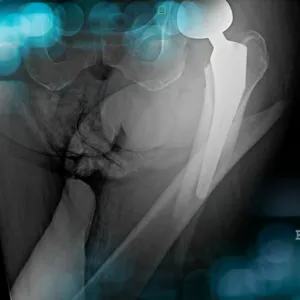

The goals of this clinical case are to discuss the periprostetic femoral fractures and their treatments